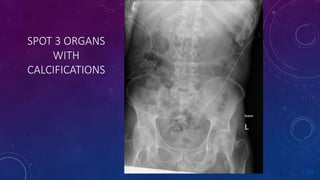

SPOT 3 ORGANS

WITH

CALCIFICATIONS

Gall stone

Calcific pancreatiits

Penile calcification

• #73 Gall stone Calcific pancreatiits Penile calcification